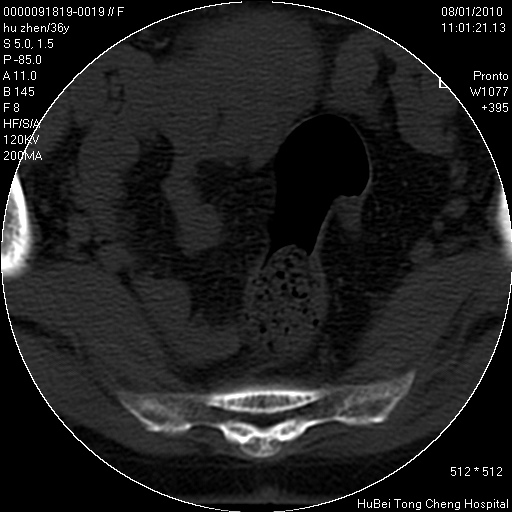

患者 女,36岁。右侧腰腿痛半月余。腰骶椎mr平扫偶然发现骶椎异常信号。

临床诊断:1)腰椎间盘突出症。2)骶椎肿瘤性病变?

骶椎ct平扫(层厚、层距均为5mm),图像如下:

考虑s1骨纤维异常增殖症。